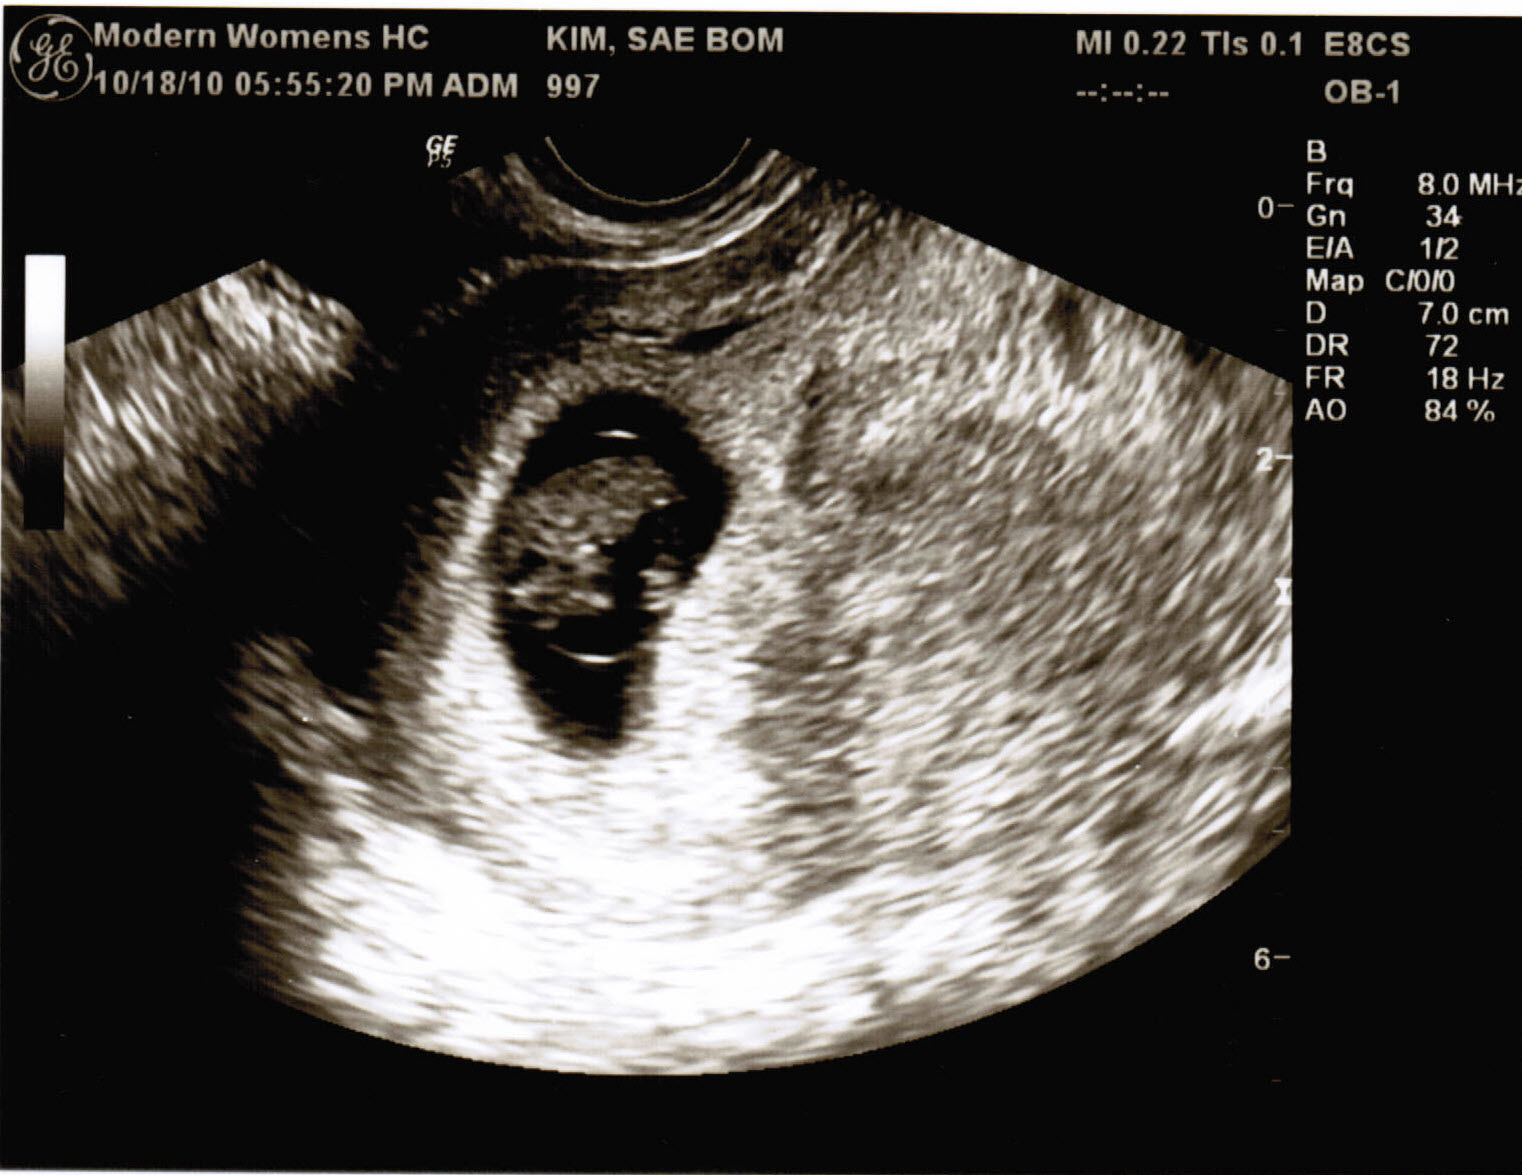

Well here it is! Don’t know if it’s a boy or girl yet because it’s puny. As you can see the doctor said around the size of a Lima bean. The only sign of life you could see was the itty bitty flicker of light which was the heart beating. Which also sounds really fast.